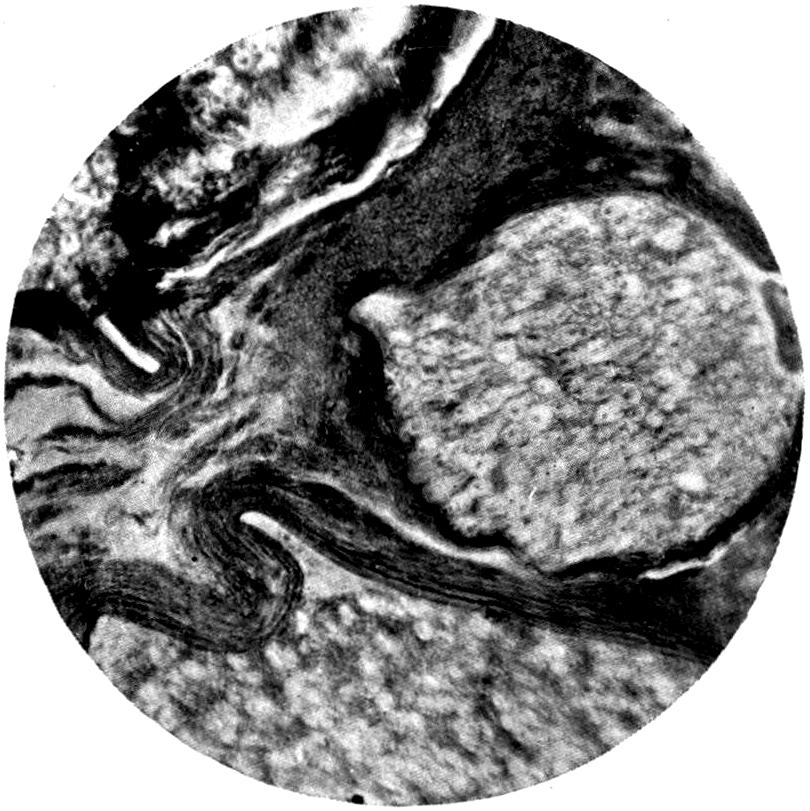

Plate I. 92

Plate II. 93

Plate III. 95